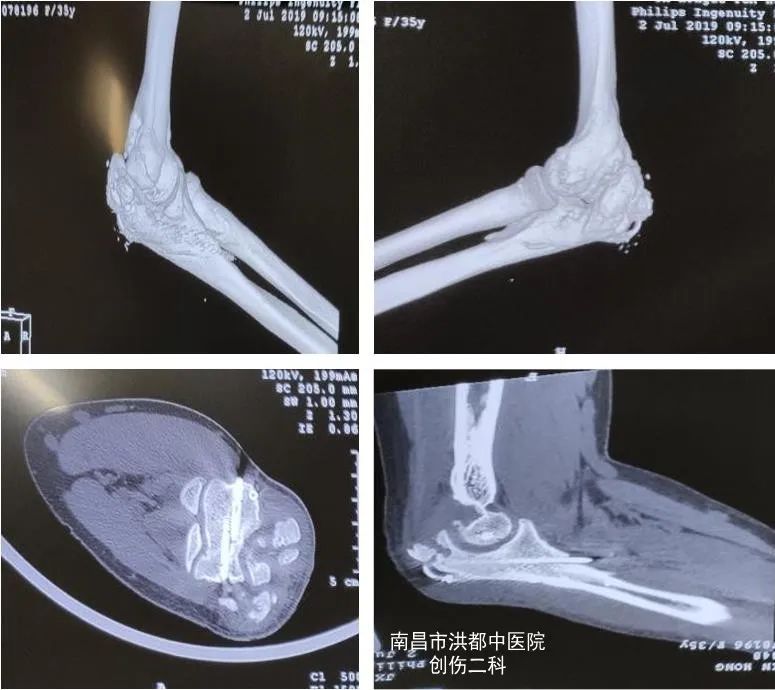

术前CT

经摄片检查发现,徐女士左肘关节周围有大量异位骨化及增生组织,遂拟“ 1.左肱骨髁部、尺骨鹰嘴骨折术后,2.左肘关节僵硬 ”收治入院。

上饶市鄱阳县35岁的徐女士,一年前因 左尺骨鹰嘴骨折、左肱骨髁部骨折 做了内固定手术,13个月后,她来到南昌市洪都中医院创伤二科,希望取出内固定物。然而,医生在门诊为徐女士检查时发现,由于术后康复训练不到位,其肘关节功能恢复不佳,不能完全弯曲和伸直,屈伸活动受限。